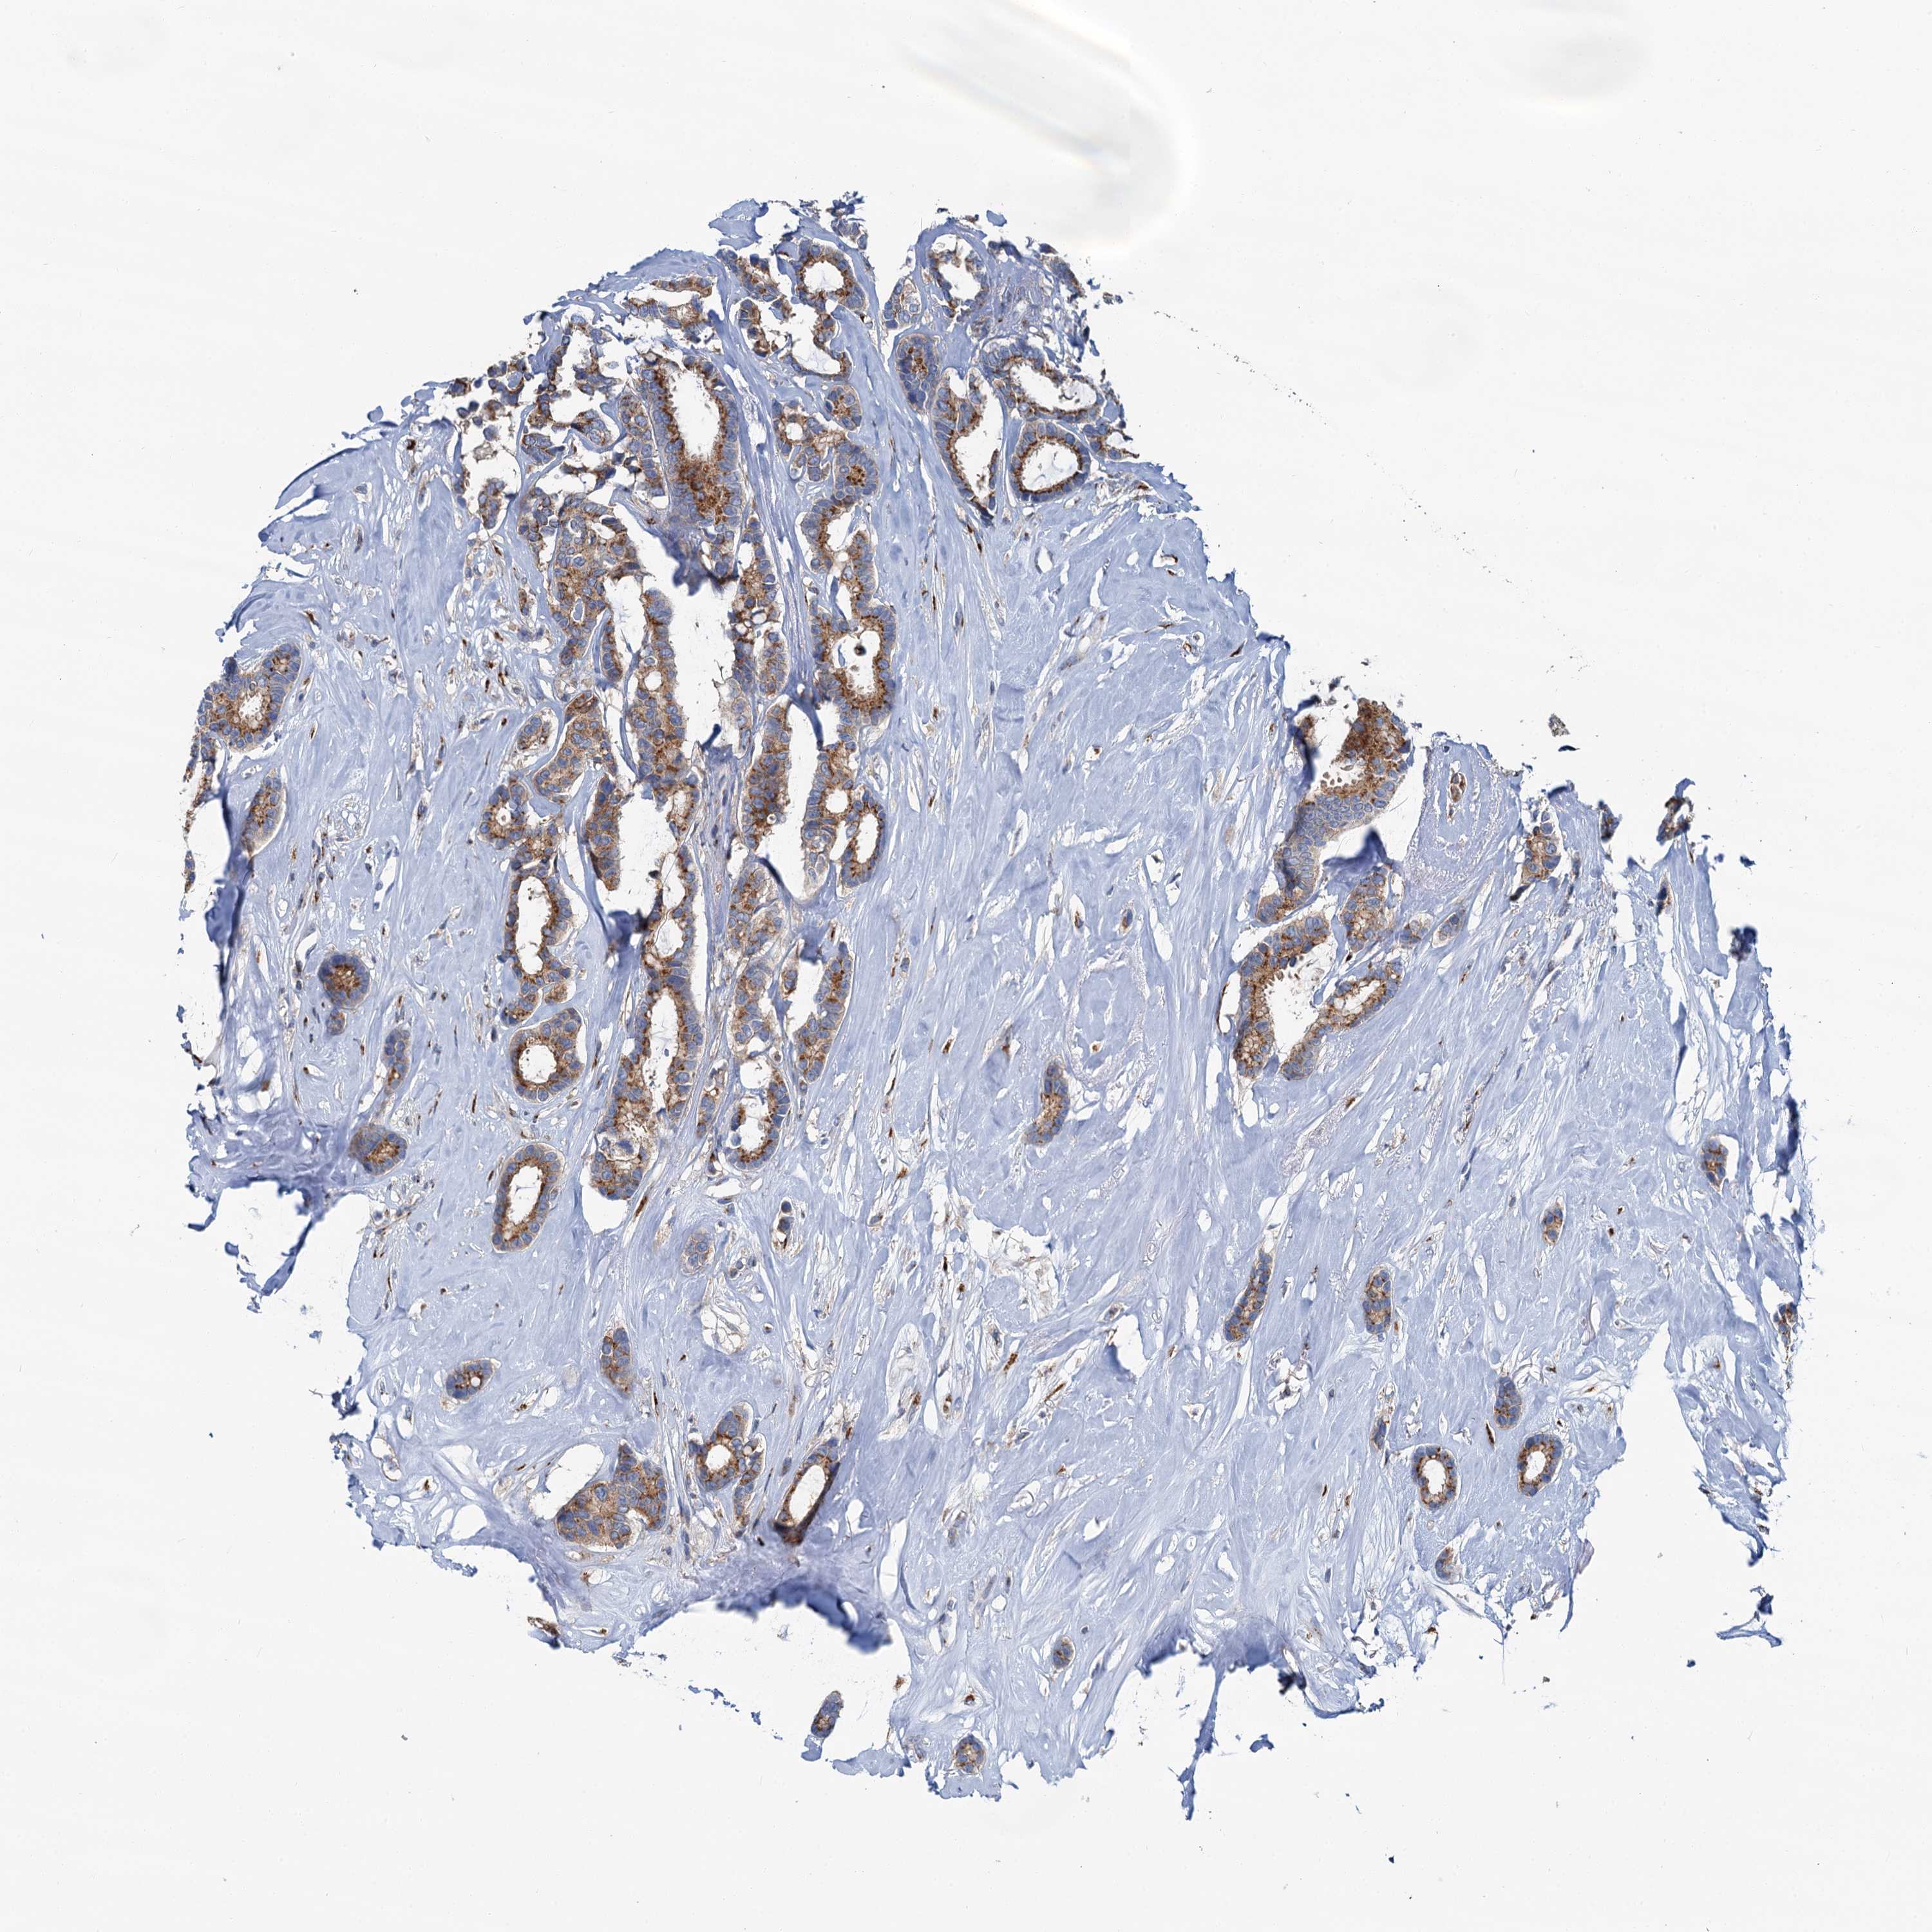

BRCA TCGA BRCA VALIDATION PROTEIN EXPRESSION